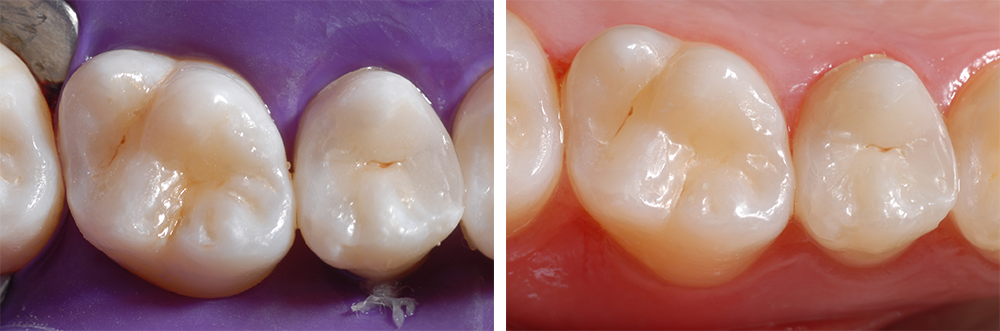

Avec un matériau composite pour la caractérisation chromatique individuelle (FinalTouch de VOCO), nous avons procédé à une caractérisation discrète des sillons occlusaux (Ill. 15), que nous avons enfin recouverts d’une couche de matériau composite. Puis nous avons polymérisé les deux obturations pendant 20 secondes. Les obturations ont été polies à l’aide de polissoirs en caoutchouc diamantés, de brossettes, de polissoirs de feutre et de pâtes de polissage.

En obtenant un très bon résultat d’obturation, nous avons pu rétablir d’importantes caractéristiques morphologiques, fonctionnelles et esthétiques (Ill. 16).

Ill. 16 : Harmonie d’esthétique et de fonctionnalité des restaurations achevées

Le matériau Admira Fusion x-tra vient sans aucun doute combler une importante lacune dans la recherche d’un matériau d’obturation esthétique. En outre, il offre au chirurgien-dentiste la possibilité de poser des obturations directes dans la zone latérale en peu de temps et avec une faible rétraction à la polymérisation. Il présente de bonnes propriétés de mise en œuvre et une excellente aptitude au polissage. La présentation du cas clinique montre clairement la simplification de la technique d’obturation qui permet de réaliser des obturations durables de bonne qualité dans la zone latérale.